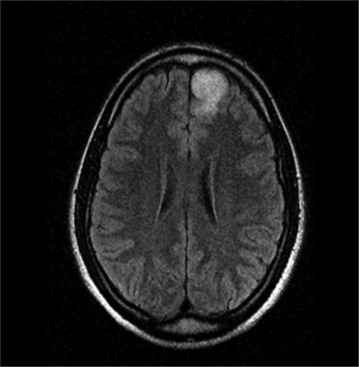

Behind the veil: Glioma presenting as delusional disorder.